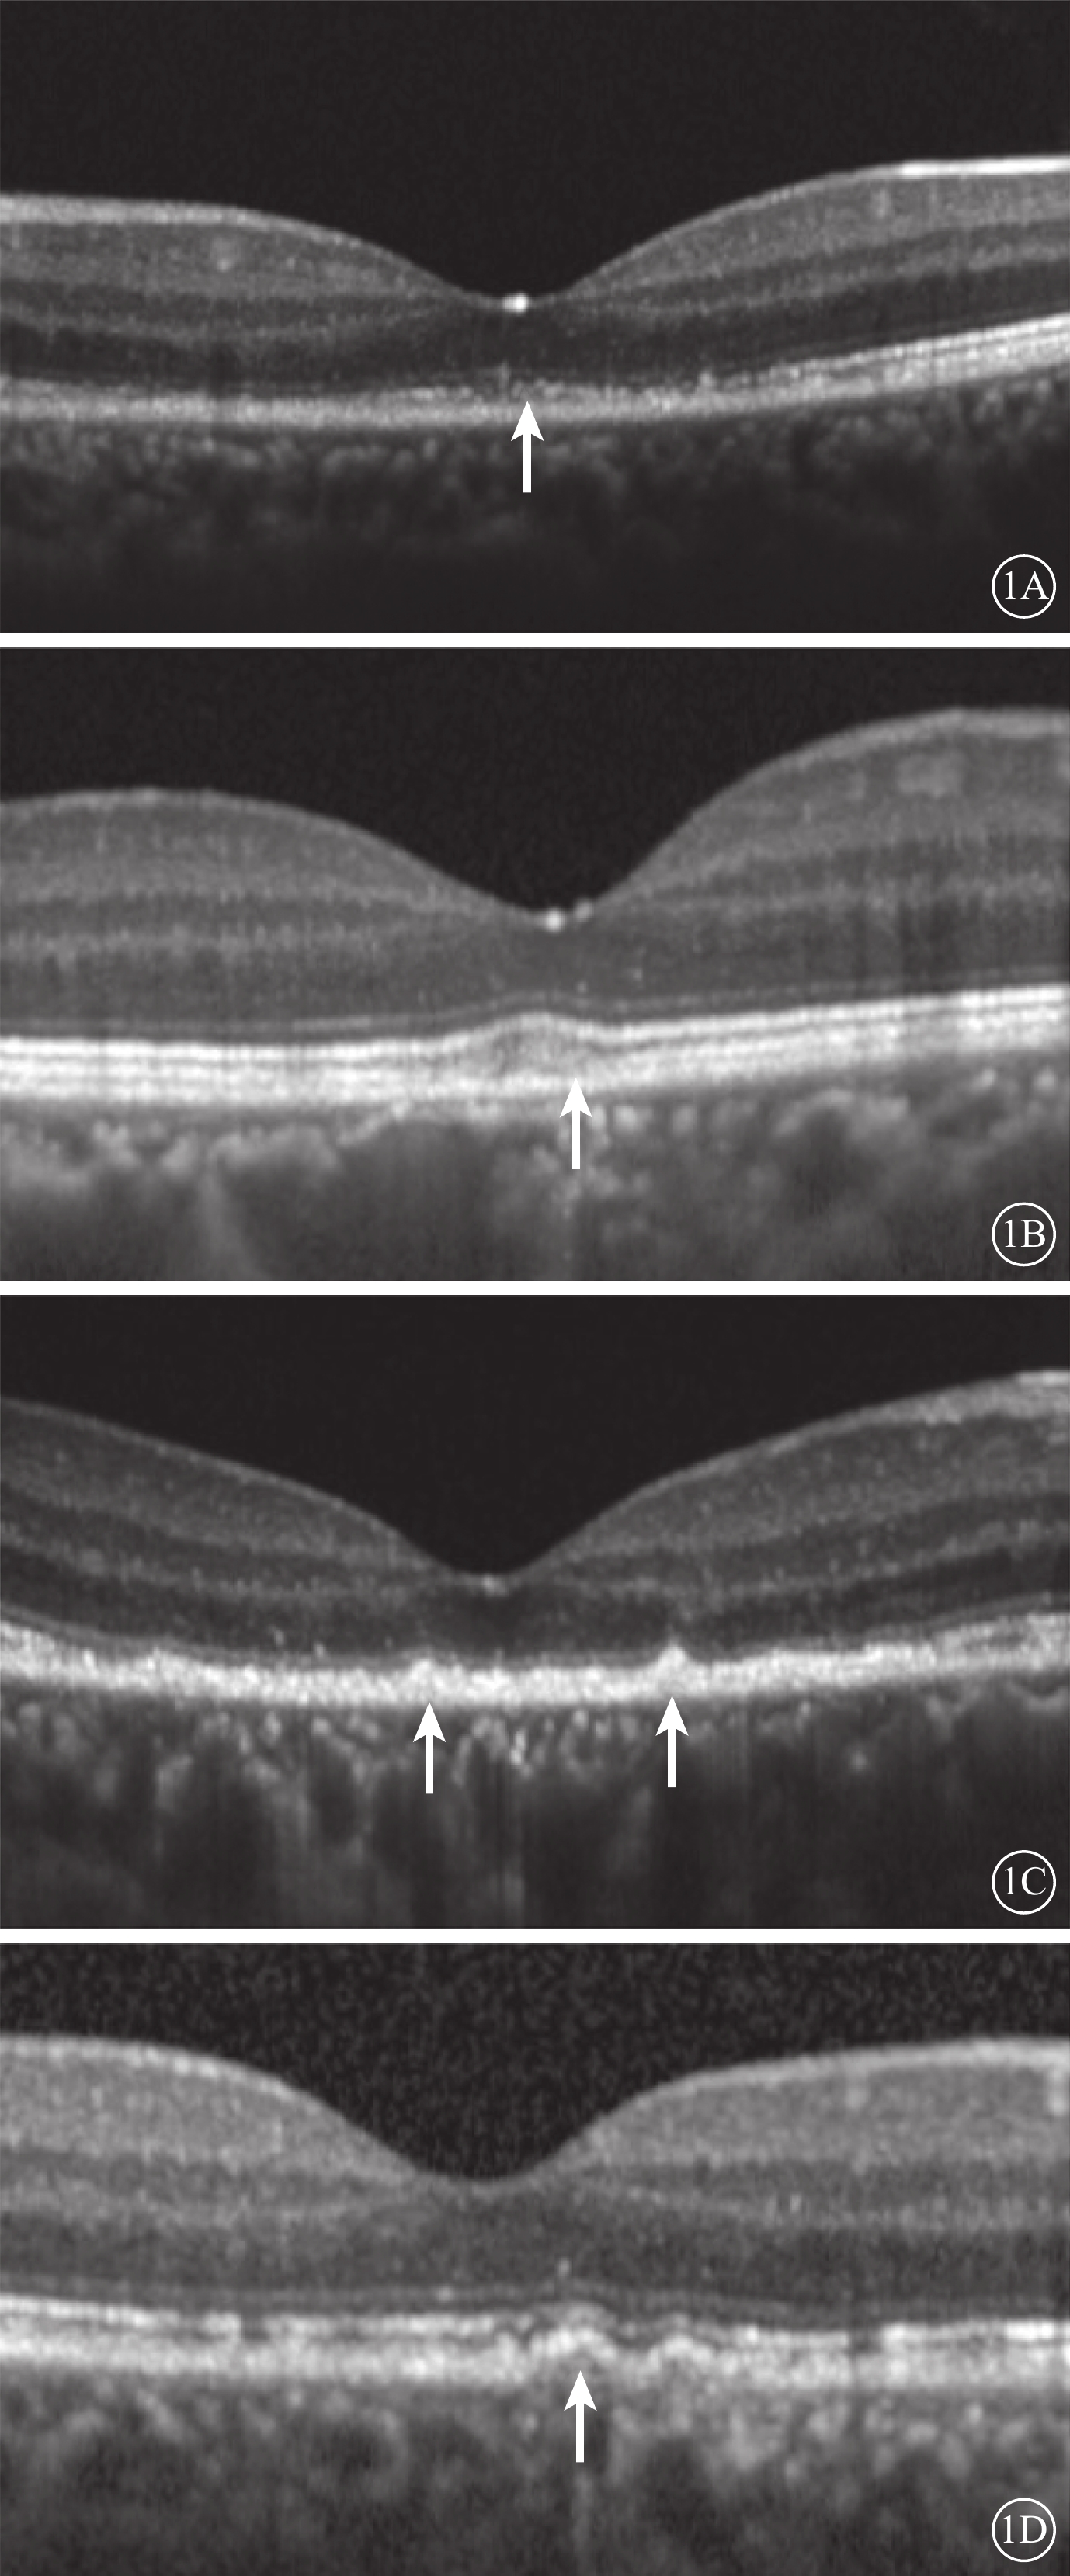

采用法國光太Supra Scan 577 nm多點掃描距陣激光器的持續激光模式或微脈沖激光模式。CLT治療參數:曝光時間0.05 s,光斑直徑100 μm,能量50~60 mW,光斑數量18~27個。SLT治療采用Supra Scan 577 nm微脈沖激光模式。治療參數:曝光時間2.00 ms,占空比5%,光斑直徑160 μm,能量250~400 mW。兩種治療方式的治療區域均為滲漏點周圍區域。所有治療均由同一位經驗豐富的眼底病醫生完成。由一位有經驗的特檢科醫生采用SD-OCT儀(Heidelberg Eye Version 1.8.6.0頻域OCT系統),對中心凹進行9 mm橫、豎單線掃描,以及黃斑區6 mm×6 mm范圍內25個斷面橫掃描,并采用隨訪模式保證每次隨訪掃描時的位置不變。選取經過中心凹的水平方向掃描圖像用于視網膜微結構評估。定性評估包括中心凹下EZ、嵌合體帶(IZ)的完整性和RPE平滑性。EZ、IZ完整性分為完整或不完整,不完整定義為OCT下相應層次連續性中斷(圖1A,1B)。RPE平滑性分為平滑或粗糙,粗糙定義為RPE局部隆起(圖1C)、RPE脫離(PED)(圖1D)、RPE增厚。定量評估包括中心凹視網膜厚度(CFT)和外核層(ONL)、內節(IS)、OS厚度。CFT定義為內界膜(ILM)內界至RPE外界的垂直距離。ONL定義為ILM外界至外界膜(ELM)內界的垂直距離。IS定義為ELM至EZ外界的垂直距離。OS定義EZ外界至RPE內界的垂直距離(圖2)。上述所有評價指標均由兩位眼科醫生分別盲態下單獨讀取,其中定量指標取兩者平均值納入統計,定性指標若存在爭議進一步討論并確定最終結果。

圖1

視網膜微結構定性評價示意圖。1A示EZ完整性破壞(白箭);1B示IZ完整性破壞(白箭);1C示RPE局部隆起(白箭);1D示PED(白箭)

圖1

視網膜微結構定性評價示意圖。1A示EZ完整性破壞(白箭);1B示IZ完整性破壞(白箭);1C示RPE局部隆起(白箭);1D示PED(白箭)

采用法國光太Supra Scan 577 nm多點掃描距陣激光器的持續激光模式或微脈沖激光模式。CLT治療參數:曝光時間0.05 s,光斑直徑100 μm,能量50~60 mW,光斑數量18~27個。SLT治療采用Supra Scan 577 nm微脈沖激光模式。治療參數:曝光時間2.00 ms,占空比5%,光斑直徑160 μm,能量250~400 mW。兩種治療方式的治療區域均為滲漏點周圍區域。所有治療均由同一位經驗豐富的眼底病醫生完成。由一位有經驗的特檢科醫生采用SD-OCT儀(Heidelberg Eye Version 1.8.6.0頻域OCT系統),對中心凹進行9 mm橫、豎單線掃描,以及黃斑區6 mm×6 mm范圍內25個斷面橫掃描,并采用隨訪模式保證每次隨訪掃描時的位置不變。選取經過中心凹的水平方向掃描圖像用于視網膜微結構評估。定性評估包括中心凹下EZ、嵌合體帶(IZ)的完整性和RPE平滑性。EZ、IZ完整性分為完整或不完整,不完整定義為OCT下相應層次連續性中斷(圖1A,1B)。RPE平滑性分為平滑或粗糙,粗糙定義為RPE局部隆起(圖1C)、RPE脫離(PED)(圖1D)、RPE增厚。定量評估包括中心凹視網膜厚度(CFT)和外核層(ONL)、內節(IS)、OS厚度。CFT定義為內界膜(ILM)內界至RPE外界的垂直距離。ONL定義為ILM外界至外界膜(ELM)內界的垂直距離。IS定義為ELM至EZ外界的垂直距離。OS定義EZ外界至RPE內界的垂直距離(圖2)。上述所有評價指標均由兩位眼科醫生分別盲態下單獨讀取,其中定量指標取兩者平均值納入統計,定性指標若存在爭議進一步討論并確定最終結果。

圖1

視網膜微結構定性評價示意圖。1A示EZ完整性破壞(白箭);1B示IZ完整性破壞(白箭);1C示RPE局部隆起(白箭);1D示PED(白箭)

圖1

視網膜微結構定性評價示意圖。1A示EZ完整性破壞(白箭);1B示IZ完整性破壞(白箭);1C示RPE局部隆起(白箭);1D示PED(白箭)